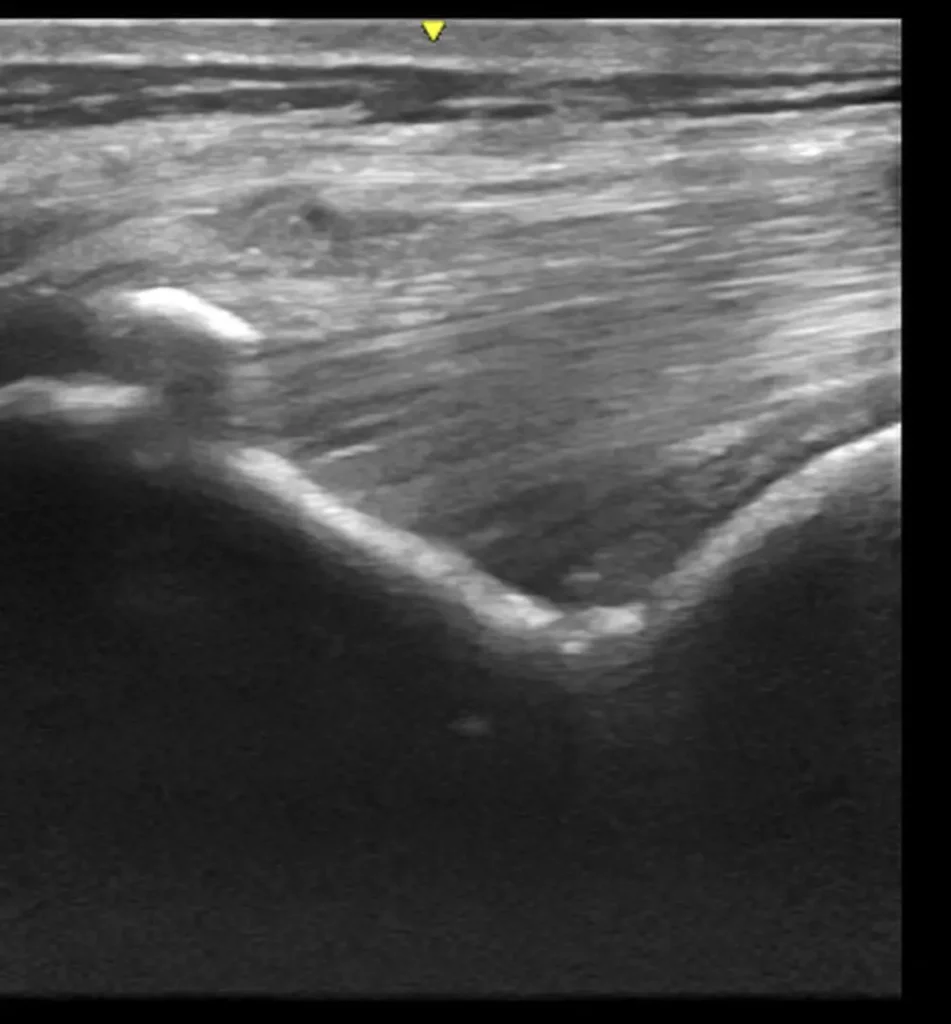

Advanced Diagnostic Imaging

We carry out diagnostic tests such as scintigraphy, magnetic resonance imaging, among others, in collaboration with equine veterinary hospitals.